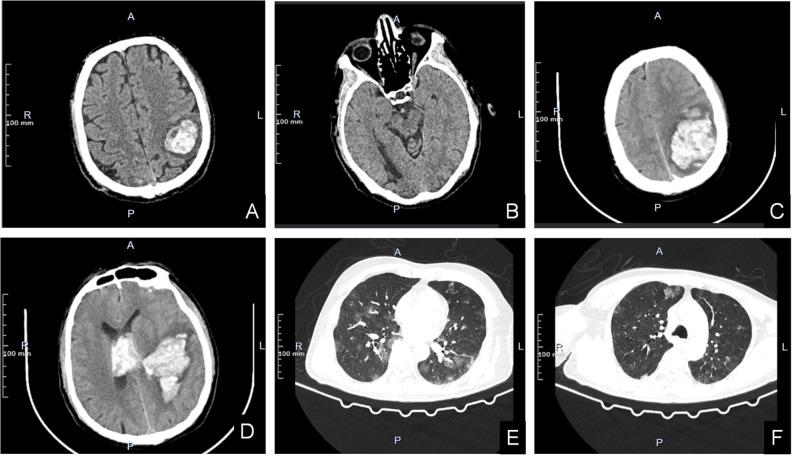

Male choriocarcinoma is an extremely rare malignant tumor. It has the characteristics of hidden onset, easy invasion and metastasis. Clinically, when choriocarcinoma is found in a patient, most of the tumor cells have metastasized to distant organs. This case reports a 65-year-old man with choriocarcinoma with two intracerebral hemorrhages as the main symptom. In this case, we consider the origin of intracranial choriocarcinoma to be testicular. We analyzed the clinical data of this patient and summarized the cases of male choriocarcinoma reported in the past, so as to arouse the attention of clinicians.

男性绒毛膜癌是一种极其罕见的恶性肿瘤。它具有起病隐匿、易于侵袭和转移的特点。临床上,当在患者身上发现绒毛膜癌时,大多数肿瘤细胞已转移至远处器官。本病例报告了一名65岁男性,以两次脑出血为主要症状的绒毛膜癌。在本病例中,我们认为颅内绒毛膜癌的起源为睾丸。我们分析了该患者的临床资料,并总结了既往报道的男性绒毛膜癌病例,以引起临床医生的重视。